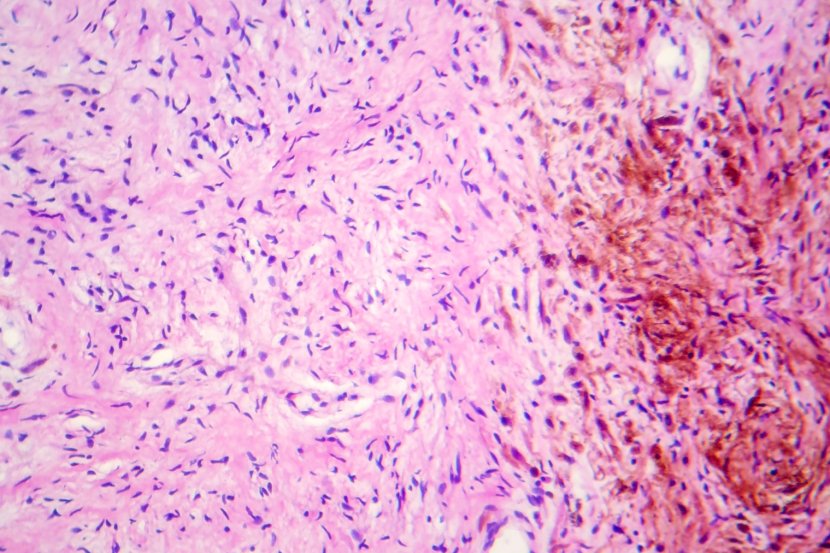

Neurofibromatoza je genetski poremećaj koji utiče na ćelije nervnog sistema i rezultira formiranjem tumora na nervnim tkivima. Ovakve tumorske mase mogu da se fomiraju u bilo kom delu našeg nervnog sistema (sami sitni nervi, kičmena moždina, mozak...).

Tumorske mase mogu biti benignog ili malignog porekla. Većinom su benigni, ali ima slučajeva u kojima ćelije alterišu u maligni oblik. Posledice su različite. Tako oboleli od neurofibromatoze mogu da imaju ozbiljne probleme sa sluhom, gubitak vida, intenzivan bol, poteškoće sa koncentracijom, fokusiranjem i učenjem, srčane ili kardiovaskularne bolesti (oštećenja krvnih i srčanih mišića), druge komplikovane deformitete izazvane kompresijom nerava pod uticajem tumorske mase.